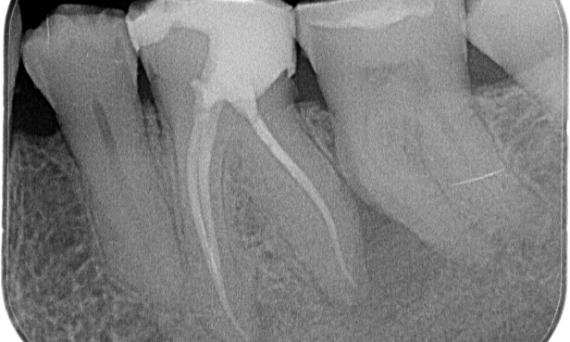

"Ich habe mich für TruNatomy entschieden, um so viel Dentin wie möglich zu erhalten, um die okklusale Belastung zu bewältigen und die Langlebigkeit des Zahns zu erhöhen." Dr. Abuelezz

Vorher: Bei der Untersuchung wurde eine Karies-Läsion am unteren rechten ersten Molaren festgestellt. Bei der röntgenologischen Untersuchung zeigte sich die Nähe der Läsion zum Pulpahorn. Zusammen mit den Hauptbeschwerden wurde die endgültige Diagnose einer chronischen irreversiblen Pulpitis gestellt.

Nachher: Die Zugangskavität wurde so konservativ wie möglich gestaltet. Da es sich um einen jungen Patienten handelte, war TruNatomy das System der Wahl. Wir mussten das Dentin so weit wie möglich erhalten, um die Fähigkeit des Zahns zur Bewältigung der okklusalen Belastung und die Langlebigkeit der endgültigen Restauration zu erhöhen.

Kairo, Ägypten